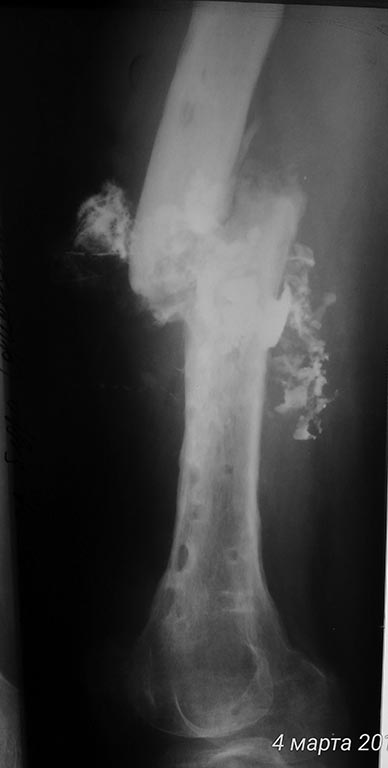

[Ortho] хронический остеомиелит с/3 бедра, свищевая форма, стадия обострения. Несросшийся перелом с/3 бедренной кости.

Имя     : fistulo1.jpg

Тип     : image/jpeg

Размер  : 36635 байтов

Url     : http://weborto.net:8080/pipermail/ortho/attachments/20170305/3a1fc87a/attachment-0002.jpg